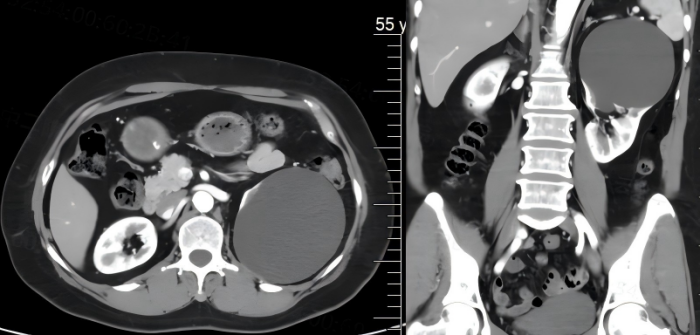

患者,女,55岁,半年前在我院外科因急性阑尾炎住院手术治疗,术中发现左肾巨大囊肿(囊肿约10cm),当时因腹腔感染未能进一步手术处理。患者出院后自觉走路及轻量运动后出现左腰部酸胀,再次入住外科。经完善术前相关检查,排除手术禁忌症,与患者及其家属充分沟通后,决定由科室主任郭勇主刀为患者实施“后腹膜腹腔镜下左肾囊肿去顶减压术”。整个手术用时短,出血量少,术后第1天,患者即可正常下地活动、正常饮食,术后恢复良好于近日出院。

术前